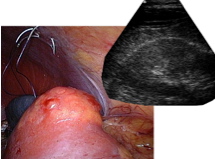

In dem Projekt werden Eingriffe an der Niere in den Mittelpunkt gestellt. Dabei werden bei einer Tumorresektion Teil der Niere entfernt.

Die Teilresektion der Niere erfolgt laparoskopisch, d.h. mit stangenartigen Instrumenten, die durch dünne Rohre in die Bauchhöhle geführt werden. Die Bauchhöhle ist dabei mit Kohlendioxid mit leichtem Überdruck aufgebläht, um gut darin arbeiten zu können. Als Bildgebung wird ausschließlich ein Videoendoskop (Laparoskop) verwendet.

Das Videoendoskop kann intraoperativ nur Oberflächenbilder liefern und keine Bilder über die interne Struktur der Niere. Eine intraoperative Echtzeitbildgebung kann durch Ultraschall erreicht werden. Jedoch sind weder das laparoskopische Ultraschall noch das transkutane Ultraschall geeignet.